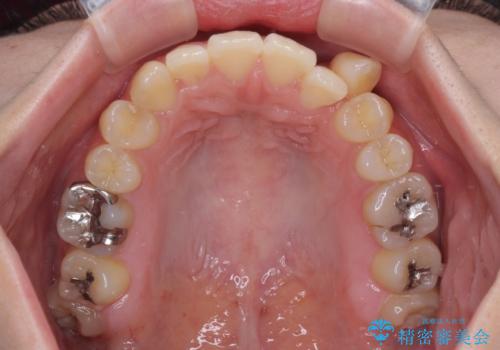

- 上顎の八重歯やデコボコを気にして来院された患者様です。

上顎歯列が狭窄していたため、急速拡大装置により上顎骨を側方に拡大しながら、ワイヤー装置にて矯正治療を行うこととしました。

上顎骨を拡大することで、八重歯やデコボコを歯列に収めることができ、下顎の歯が外に位置していた奥歯の咬み合わせも改善することができました。

スペースも短期間に獲得できるため、1年程度で治療を終えることができました。